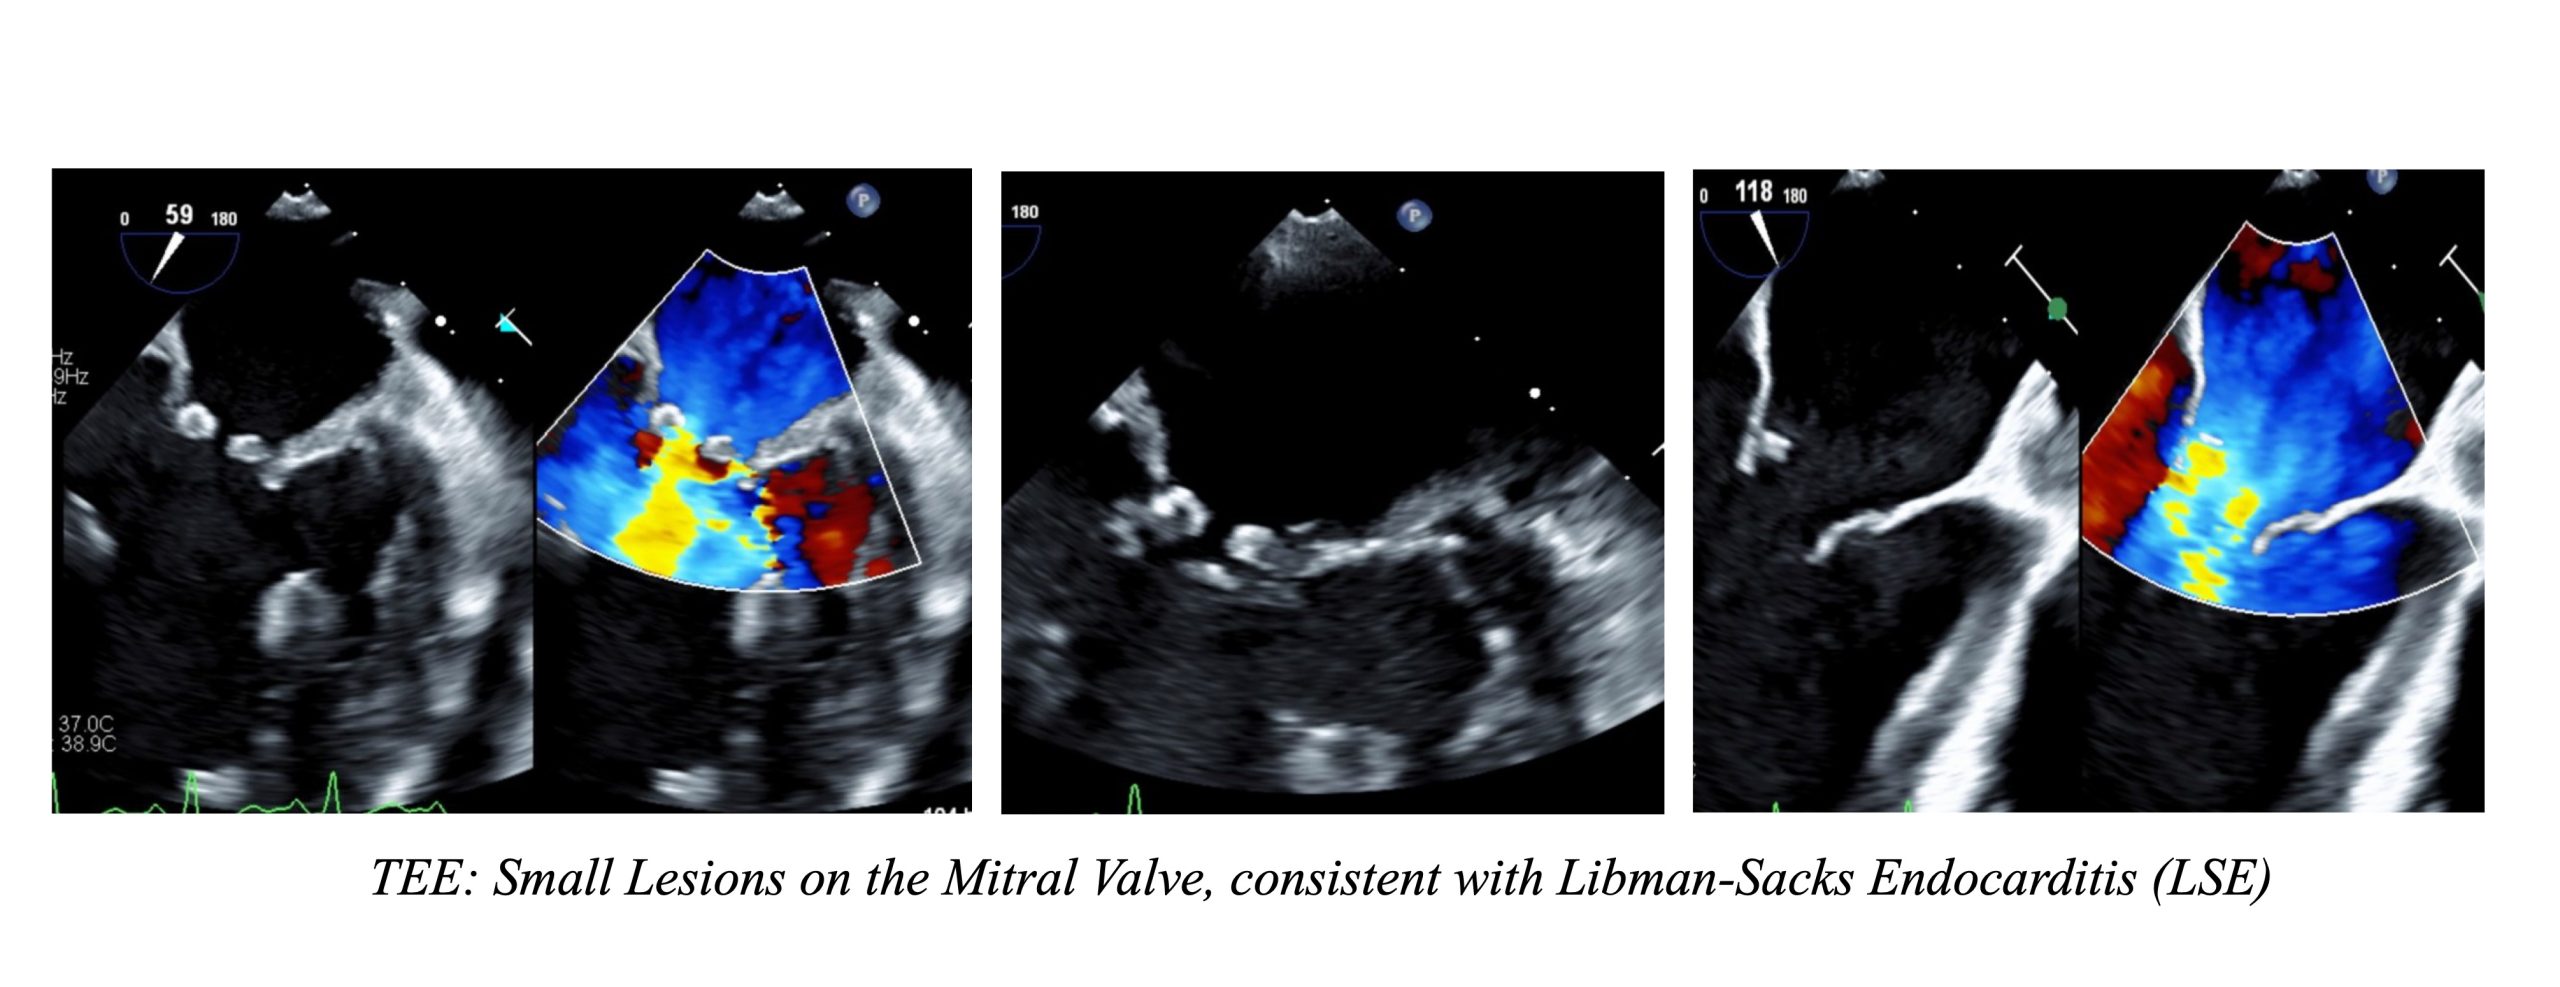

Case Presentation: A 25-year-old female with a history of Systemic Lupus Erythematosus (SLE), lupus nephritis, cardiomyopathy, transient ischemic attack, and epilepsy presented as an ICU transfer for Altered Mental Status (AMS). The patient initially presented to an outside hospital for this complaint, which was attributed to seizures. Her course was complicated by severe hypotension, again believed to be precipitated by seizures, leading to cardiac arrest. Following the return of spontaneous circulation, she was transferred to our institution due to undifferentiated shock and ongoing encephalopathy. At the time of admission, CT head and EEG were negative. MRI brain showed multifocal punctate lesions. Cardiac MRI and Transthoracic Echocardiogram (TTE) revealed no valvular vegetation. An infectious workup came back negative. Meanwhile, the patient’s AMS continued to improve, and she was transferred to the general medical floor under hospitalist care. A repeat MRI after five days showed persistent Diffusion-Weighted Imaging hyperintensities in bilateral border zones and bilateral cerebellar hemispheres. At this point, neurology was consulted given concern for stroke. Transesophageal Echocardiogram (TEE) was recommended to rule out endocarditis. TEE showed small, fixed masses on the mitral valve consistent with Libman-Sacks Endocarditis (LSE). Cardiology was consulted and the patient was started on heparin for anticoagulation.

Discussion: This case highlights the rare occurrence of LSE and the essence of a multidisciplinary approach in patient care. It also emphasizes the need for hospital medicine providers to be vigilant of anchoring bias, continually reassessing initial diagnoses and pursuing additional workup if warranted. LSE is a non-infectious endocarditis characterized by the deposition of sterile platelet thrombi on heart valves. It is a rare condition that is often discovered during autopsies, with prevalence rates from 0.9% to 1.6%. Vegetations associated with LSE can dislodge, posing a high risk of systemic embolism. TEE is the most sensitive imaging for detecting small lesions related to LSE. Treatment involves systemic anticoagulation and addressing the underlying cause, such as malignancy or SLE itself. For our patient, a key diagnostic challenge was distinguishing between the various mechanisms contributing to the patient’s condition. Her presentation was initially attributed to postictal changes after seizures. Even the initial MRI results were attributed to hypoxic brain injury following cardiac arrest, and neurology has signed off. However, a repeat MRI five days later showed persistent multifocal infarcts, raising concern for embolic phenomena. This finding prompted further evaluation for other causes of multifocal stroke, including a second neurology consultation and an ischemic workup. TEE was obtained due to its higher sensitivity compared to TTE and cardiac MRI, both of which already resulted negative. TEE revealed small lesions on the mitral valve, which confirmed the diagnosis of LSE in the setting of multifocal infarcts and negative blood cultures.